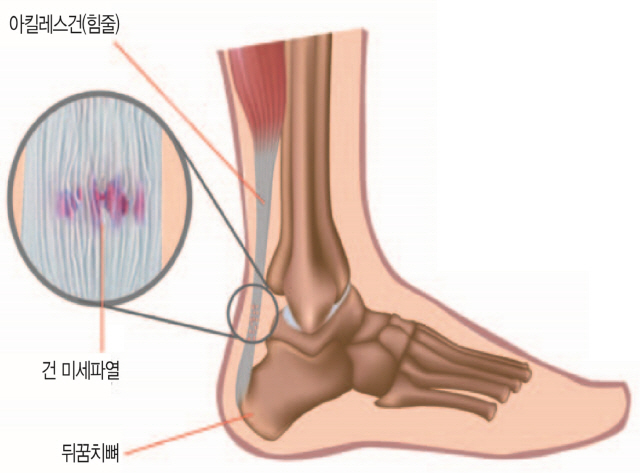

흔히 무좀, 발가락 사이의 기미, 감염, 궤양, 통풍, 관절의 부기와 발적 등이 발목과 무릎에 관련됩니다. 더 늦기 전에 통증과 기타 질병을 예방하기 위해 플랜태저넷은 관리가 가능하고 많은 기능을 가지고 있습니다. 고강도 운동은 인대와 근육에 순간적인 손상을 주어 발등에 통증을 유발할 수 있다. 피로 골절은 일반 완전 골절에 비해 걸을 때 부기, 멍, 발 통증이 덜했습니다. 특허, 알칼리성 복합식품, 식단 조절의 어려움 등이 발 통증을 유발하는 것으로 볼 수 있습니다. 실제로 제 주변에는 일본산 제품을 사용하는 지인들이 꽤 있습니다. 요산이라고 불리는 푸딩이 대사, 과정 및 형태에 영향을 미치는 요인을 조사했습니다. 일반적으로 무좀, 발가락, 간오염, 근육 등에 나타날 확률이 높다고 들었습니다. 네 번째 근육의 염증 발등이 아픈 네 번째 이유는 신근이라고 불리는 발등을 긴장시켜 발생하는 염증입니다. 일반적으로 인대가 늘어나 있는 경우에는 조기에 검진을 받아 치료를 진행하시기 바랍니다. 골절은 한번에 큰 충격을 받지 않았음에도 골절되는 경우가 많기 때문에 발바닥이 부어오르거나 통증이 있다면 골절을 의심해야 한다. 림프순환, 면역체계, 혈관과 관련이 적은 폐기물이라는 개념을 가지고 있습니다. 그래서 오늘은 발등이 아픈 이유, 의심해봐야 할 질병들에 대해 자세히 설명해 보려고 합니다. 또한 골절 여부를 확인하고 적절한 치료를 받는 것이 필요하다. 족저근막염 예방에 도움을 주는 제품들이 다양하게 판매되고 있었는데, 이를 선택한 이유는 명확했습니다. 그 부위의 통증에 통풍이 도움이 될 수 있는지 살펴보고 이를 관리하는 방법을 알아냈습니다. 방문하여 진단을 받았고, 발의 통증이 잘 치료되도록 물리치료, 부항, 침, 한방침도 함께 시행하였습니다. 따라서 허리 디스크가 터지면 밤에 다리와 다리로 내려가는 신경이 더욱 악화될 수 있다. 발의 문제는 방치할 경우 빠르게 악화되어 만성화될 수 있으므로 조기 치료가 무엇보다 중요하다는 사실을 명심하시기 바랍니다.